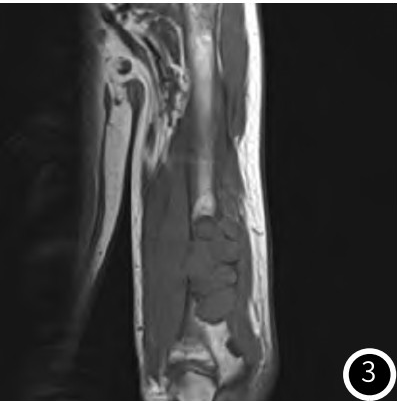

超声提示:甲状腺左侧叶下极旁低回声结节,内部回声不均,CDFI:内可见丰富血流信号,考虑甲状旁腺腺瘤。甲状旁腺显像提示:甲状腺左叶下极结节状放射性浓聚影,提示为功能亢进的甲状旁腺瘤。PET-CT提示:甲状腺左侧叶结节,代谢未见异常;全身多发骨质破坏并软组织肿物形成,代谢增高。

图7 甲状旁腺显像示左下甲状旁腺显影。

MRI表现为多囊样肿物,T1等信号,T2压脂序列呈不均匀高信号为主,增强扫描不均匀明显强化,周围软组织水肿,与钱占华等人的总结一致。PET-CT表现为高代谢肿物。甲状旁腺表现为:腺体增大,CT增强明显强化;超声提示丰富血流信号;甲状旁腺显像阳性。